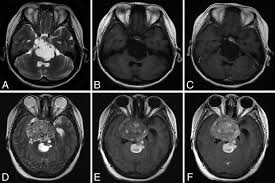

Истинный диагноз хордомы ставится патологоанатомическим исследованием. Но радиологическая визуализация; рентген, компьютеризированная томография (КТ) и магнитно-резонансная томография помогают определить характеристики опухоли. В исследованиях, проводимых с помощью современных технологий, хордома и хондросаркома не могут быть надежно отделены друг от друга с помощью рентгенологических исследований до операции. Хордомы и хондросаркомы опухоли мезенхимального происхождения, но имеют разные биологические особенности. Их можно увидеть на одной нервной оси. Классическим видом черепных хордом это скат в виде симметричной инфильтрирующей опухоли. На томографии будет видно, что опухоль из мягкой ткани вызывает деструкцию костной ткани. КТ лучше показывает различие, особенно при демонстрации инвазии черепных отверстий.

Магнитно-резонансная томография (МРТ) золотой стандарт визуализации хордом. МРТ четко показывает, что, хордомы возникают из ската и видны как однородные, гипоинтенсивные поражения, которые вызывают экспансивную деструкцию кости. В Т1-взвешенных исследованиях они гетерогенные, гипоинтенсивные на Т2-взвешенных изображениях они представляют собой гетерогенные, гиперинтенсивные очаги, которые могут удерживать различное количество контраста.

Хордомы наиболее распространенные опухоли в скате после метастазов. Нормальный скат имеет низкую интенсивность сигнала на МРТ, а сигнал Т1 с возрастом еще больше снижается из-за увеличения количества жира в костном мозге. При МРТ-исследованиях видно, что хордомы растут, образуя дольки. Хордомы и хондросаркомы легко отличить от других опухолей, расположенных в скате. Патологиями, включенными в дифференциальный диагноз, являются менингиомы, инвазивные аденомы гипофиза, плазмоцитомы, метастатические опухоли, карциномы клиновидной пазухи, карциномы носоглотки, лимфомы, гранулематозные заболевания и опухоли хряща. Однако нет надежного признака, который мог бы отличить хордомы от хондросарком или хондроидных подтипов с другим прогнозом.